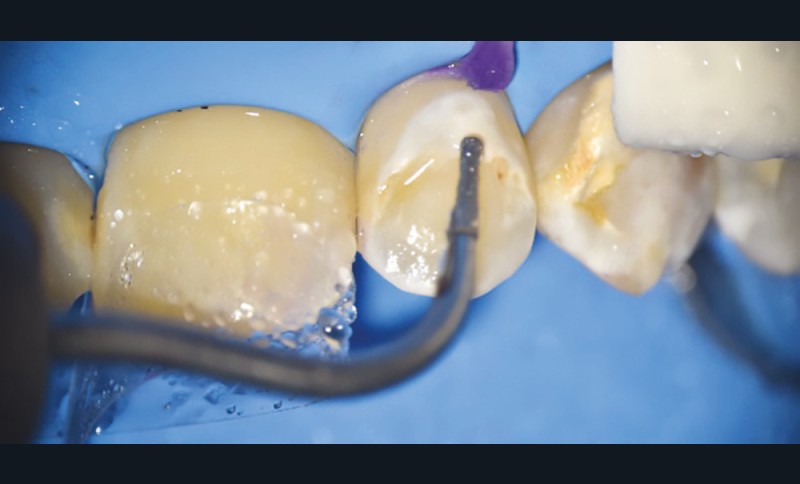

- soit de façon invasive a minima. Cette économie tissulaire peut se faire notamment avec l’utilisation de fraises adaptées et minimalement invasives (fig. 4).

• Traitement invasif a minima : il concerne les lésions carieuses cavitaires ou non avec atteinte dentinaire (à partir du 1/3 moyen dentinaire), soit ICDAS 3 à 6. Dans ce cas, la priorité est de préserver la dent d’une effraction pulpaire éventuelle (recommandations de l’ESE) [4]. C’est pourquoi, lors du traitement de lésions carieuses profondes (ICDAS 4 à 6), il faut dans tous les cas réaliser une éviction sélective, réaliser une préparation a minima (favoriser les préparations de type fente (« slot ») ou tunnel lorsque l’indication se pose) et utiliser un matériau de restauration de choix, soit composite, soit un ciment verre ionomère (CVI), soit des matériaux à base de silicate de calcium ou encore les nouveaux composites enrichis en minéraux (fig. 7 à 9). Ces préparations a minima peuvent être réalisées avec des fraises de petits diamètres (fig. 10 et 11).